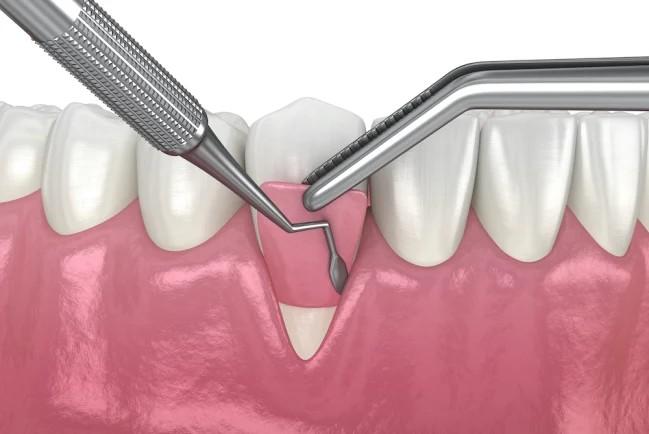

- Gusi yang mengalami penurunan (resesi) perlu dilakukan perawatan. Dokter gigi akan mengawali perawatan dengan melakukan pembersihan karang gigi dan penghalusan akar gigi yang terekspos / tidak tertutup lagi oleh gusi. Apabila tulang penyokong gigi dan gusi ini mengalami kehilangan / penurunan tinggi tulang yang ekstrim maka pembersihan dilakukan dengan membutuhkan pembedahan agar alat dapat mencapai saku gusi yang lebih dalam lagi. Setelah dilakukan pembersihan plak dan karang gigi pada permukaan luar gigi, akar gigi, dan saku gusi untuk memperbaiki estetika dapat dilakukan berbagai cara seperti gingivoplasty, gingival graft, dan artificial gingiva. Gingivoplasty adalah suatu prosedur pembedahan yang dilakukan untuk memperbaiki bentuk dan kontur gingiva. Gingival graft / cangkok gusi merupakan prosedur untuk memperbaiki penampilan gusi yang turun dengan menambahkan jaringan gusi pada daerah yang mengalami penurunan gusi. Jaringan gusi yang digunakan dapat diambil dari gusi di sekitar daerah tersebut atau mengambil sebagian gusi dari langit-langit mulut. Sedangkan artificial gingiva adalah gusi tiruan yang terbuat dari bahan silikon. Lakukan kunjungan rutin ke RSGMP Nala Husada minimal 6 bulan sekali.